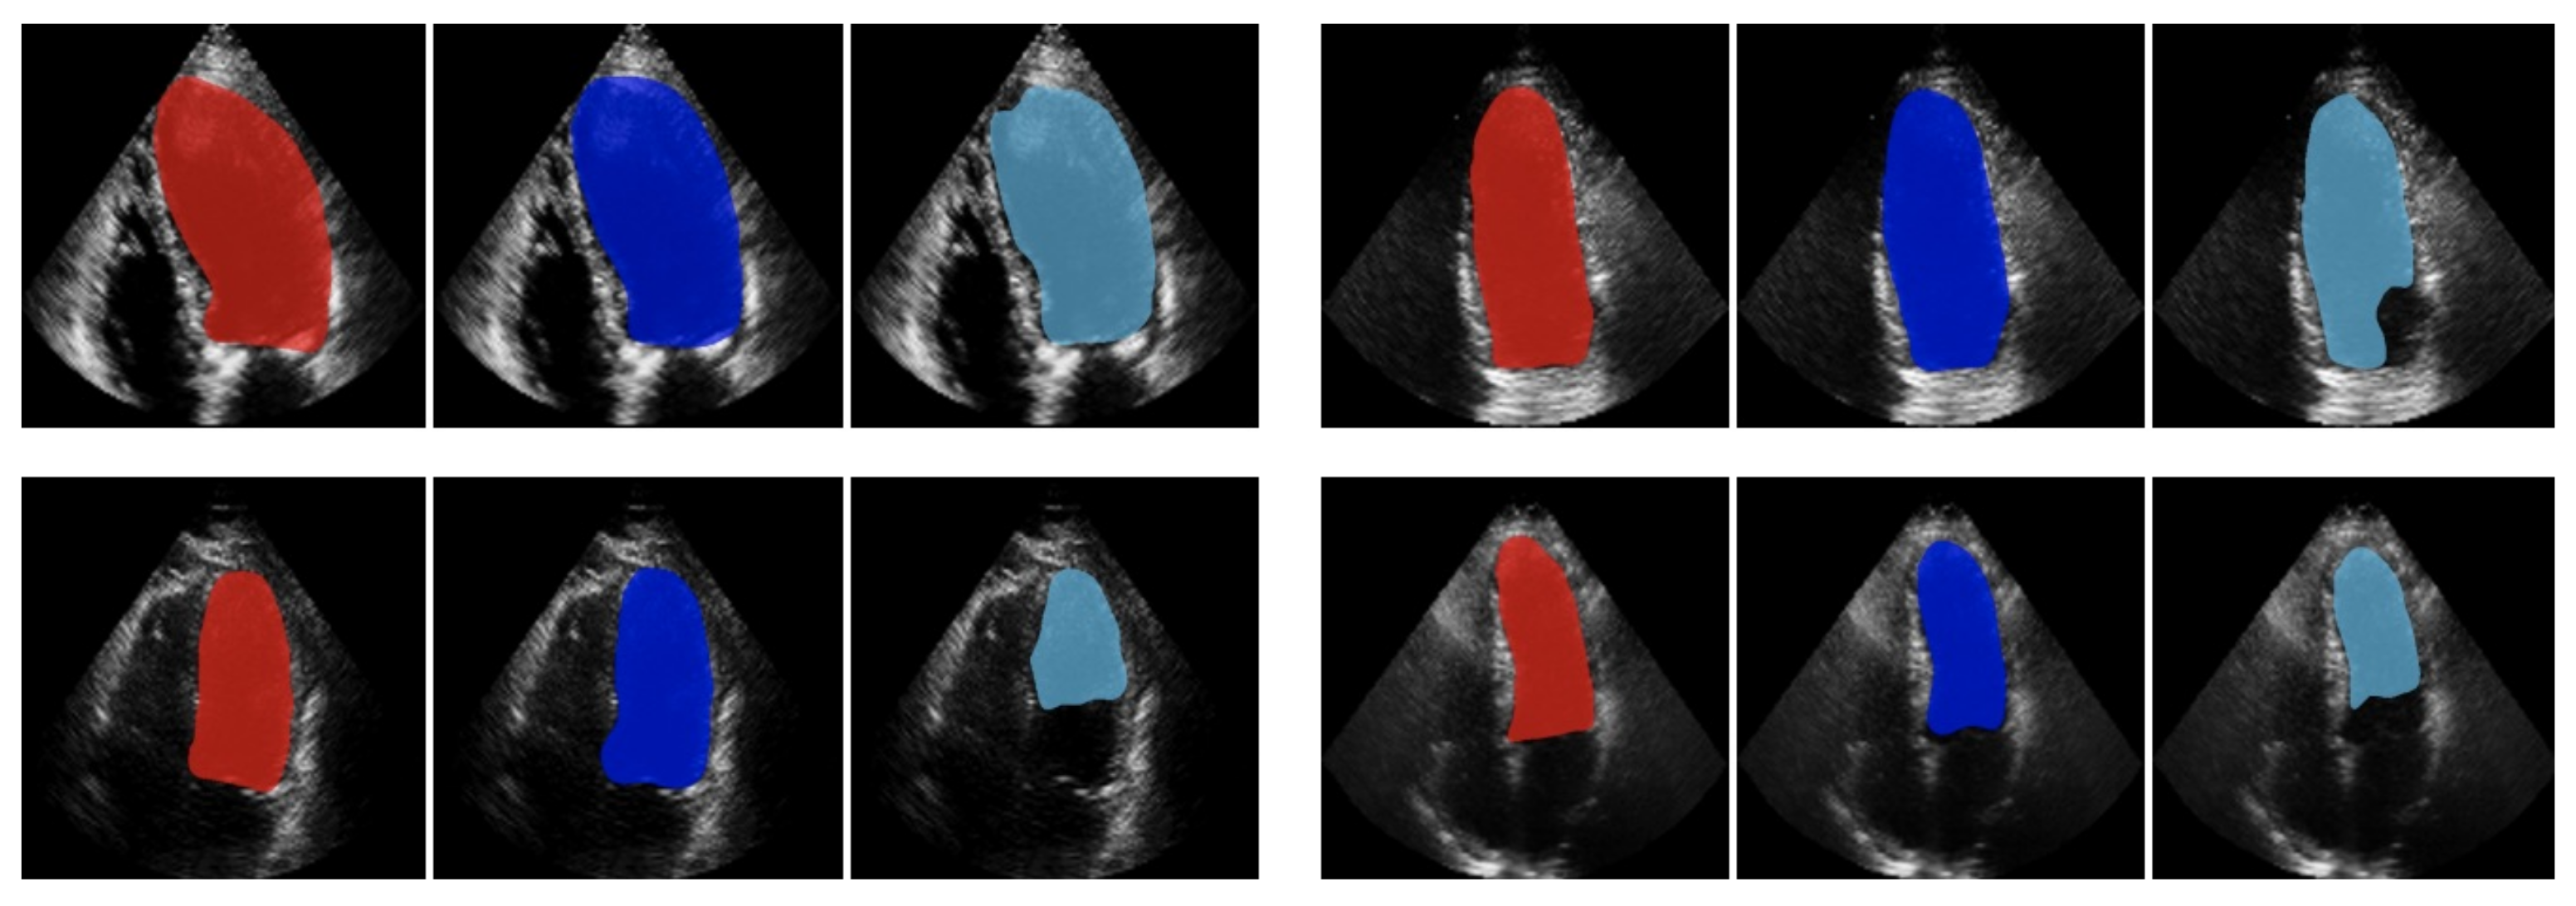

- Smistad, E.; Østvik, A. 2D left ventricle segmentation using deep learning. In Proceedings of the 2017 IEEE International Ultrasonics Symposium (IUS), Washington, DC, USA, 6–9 September 2017; pp. 1–4. [Google Scholar]

- Zyuzin, V.; Sergey, P.; Mukhtarov, A.; Chumarnaya, T.; Solovyova, O.; Bobkova, A.; Myasnikov, V. Identification of the left ventricle endocardial border on two-dimensional ultrasound images using the convolutional neural network Unet. In Proceedings of the 2018 Ural Symposium on Biomedical Engineering, Radioelectronics and Information Technology (USBEREIT), Yekaterinburg, Russia, 7–8 May 2018; pp. 76–78. [Google Scholar]

- Zyuzin, V.; Chumarnaya, T. Comparison of Unet architectures for segmentation of the left ventricle endocardial border on two-dimensional ultrasound images. In Proceedings of the 2019 Ural Symposium on Biomedical Engineering, Radioelectronics and Information Technology (USBEREIT), Yekaterinburg, Russia, 25–26 April 2019; pp. 110–113. [Google Scholar]

- Smistad, E.; Salte, I.M.; Dalen, H.; Lovstakken, L. Real-time temporal coherent left ventricle segmentation using convolutional LSTMs. In Proceedings of the IEEE International Ultrasonics Symposium, Virtual Symposium, 11–16 September 2021. [Google Scholar]